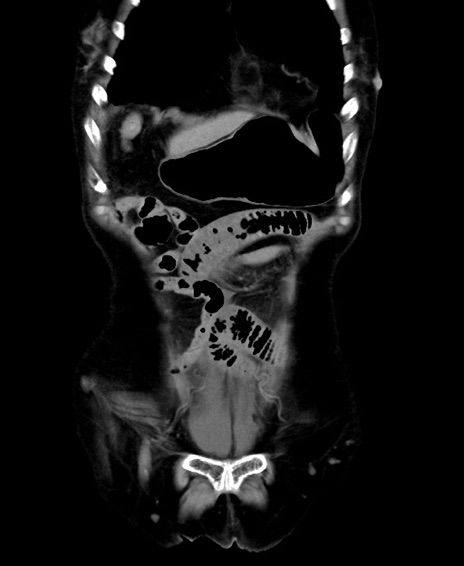

他院CT

横断像